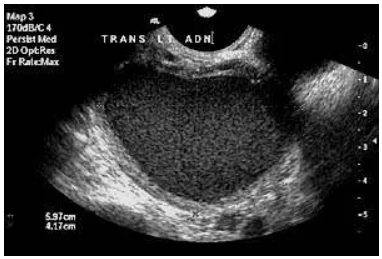

The following photos were taken at the laparoscopy of a woman with an endometrioma inside both her ovaries. They show what an endometrioma looks like on ultrasound:

the brown fluid that comes out when the ovary is opened. The brown fluid gives an endometrioma an even grainy appearance on ultrasound.

Women with more severe endometriosis may have an endometrioma. These are also called chocolate cysts.

An endometrioma:

Grows inside the ovary, which can make the ovary larger

Has a thick wall

Often contains thick brown fluid (old blood)

On ultrasound, an endometrioma can have a more even, grainy appearance. At laparoscopy, opening an endometrioma can allow the brown fluid to come out, and the cyst wall may be seen inside the ovary and removed.